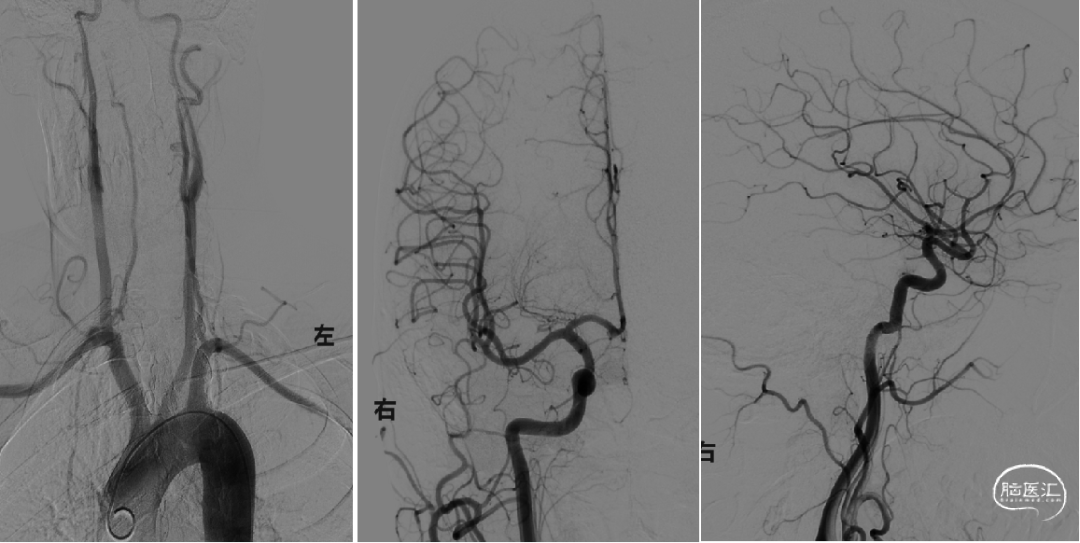

主动脉弓和全脑动脉造影示:左侧大脑中动脉闭塞,结合患者病史及造影结果,考虑为本次责任血管,故与患者家属沟通后行动脉导管抽吸、支架取栓术,必要时行球囊扩张支架置入血管成形术。

造影显示左侧大脑中动脉闭塞,右侧颈内动脉及后循环血管未见明显异常;左侧大脑前动脉通过软膜支部分代偿。

将6F 132cm Cat 6中间导管送至左侧颈内动脉末端,将Synchro微导丝及取栓支架微导管通过闭塞段血管,经微导管造影提示进入血管真腔,引入Trevo ProVue 4*20mm取栓支架,精确定位后缓慢回撤微导管释放取栓支架覆盖闭塞段血管,远端血流即刻恢复,等待5分钟血栓与支架充分嵌合,关闭灌注系统,注射器持续负压抽吸中间导管,将中间导管跟进至取栓支架近端,将取栓支架及中间导管整体撤出体外,支架内可见少许碎屑样血栓。